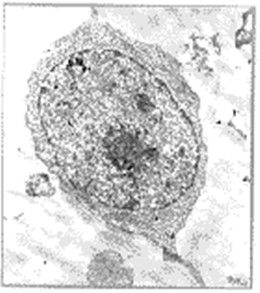

MCAB1975年,Kohler和Milstein發現將小鼠骨髓瘤細胞和綿羊紅細胞免疫的小鼠脾細胞進行融合,形成的雜交細胞既可產生抗體,又可無限增殖,從而創立了單克隆抗體雜交瘤技術。這一技術上的突破不僅為醫學與生物學基礎研究開創了新紀元,也為臨床疾病的診、防、治提供了新的工具。

單克隆抗體的生產可採用動物體作為生物反應器或採用人工生物反應器培養雜交瘤細胞進行生產,前者可通過誘發實體瘤及腹水瘤,從腹水中提取,也可採用牛淋巴液體外循環的中空纖維培養雜交瘤細胞法,從培養液中提取McAb,後者是採用體外大量培養雜交瘤細胞,從含有McAb的培養上清中提取。